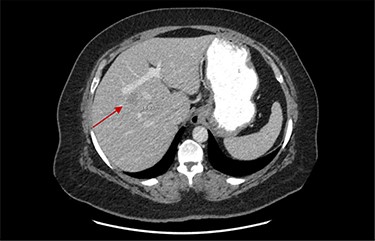

On assessment, the patient denied any symptoms related to her neuroendocrine tumor, including flushing, increased sweating, increased heart rate, wheezing, shortness of breath, diarrhea, weight loss or appetite changes. The only significant family history was a paternal and maternal grandfather with colon cancer. Imaging results were significant for computed tomography (CT) of chest demonstrating very small, but multiple, pulmonary nodules. A CT abdomen and pelvis demonstrated the known neuroendocrine tumor near the ileocecal valve (Fig. 1) as well as two poorly visualized liver lesions (Figs 2–4). The magnetic resonance imaging (MRI) demonstrated two separate one-centimeter lesions in segment 5 and 7 of the liver (Figs 5 and 6). The portal vein lacked normal left and right bifurcation; there was a circumferential right portal vein, which coursed anteriorly and superiorly and ultimately to the left lobe of the liver.

MRI image again demonstrating segment 5 metastatic lesion in close proximity to portal vein.